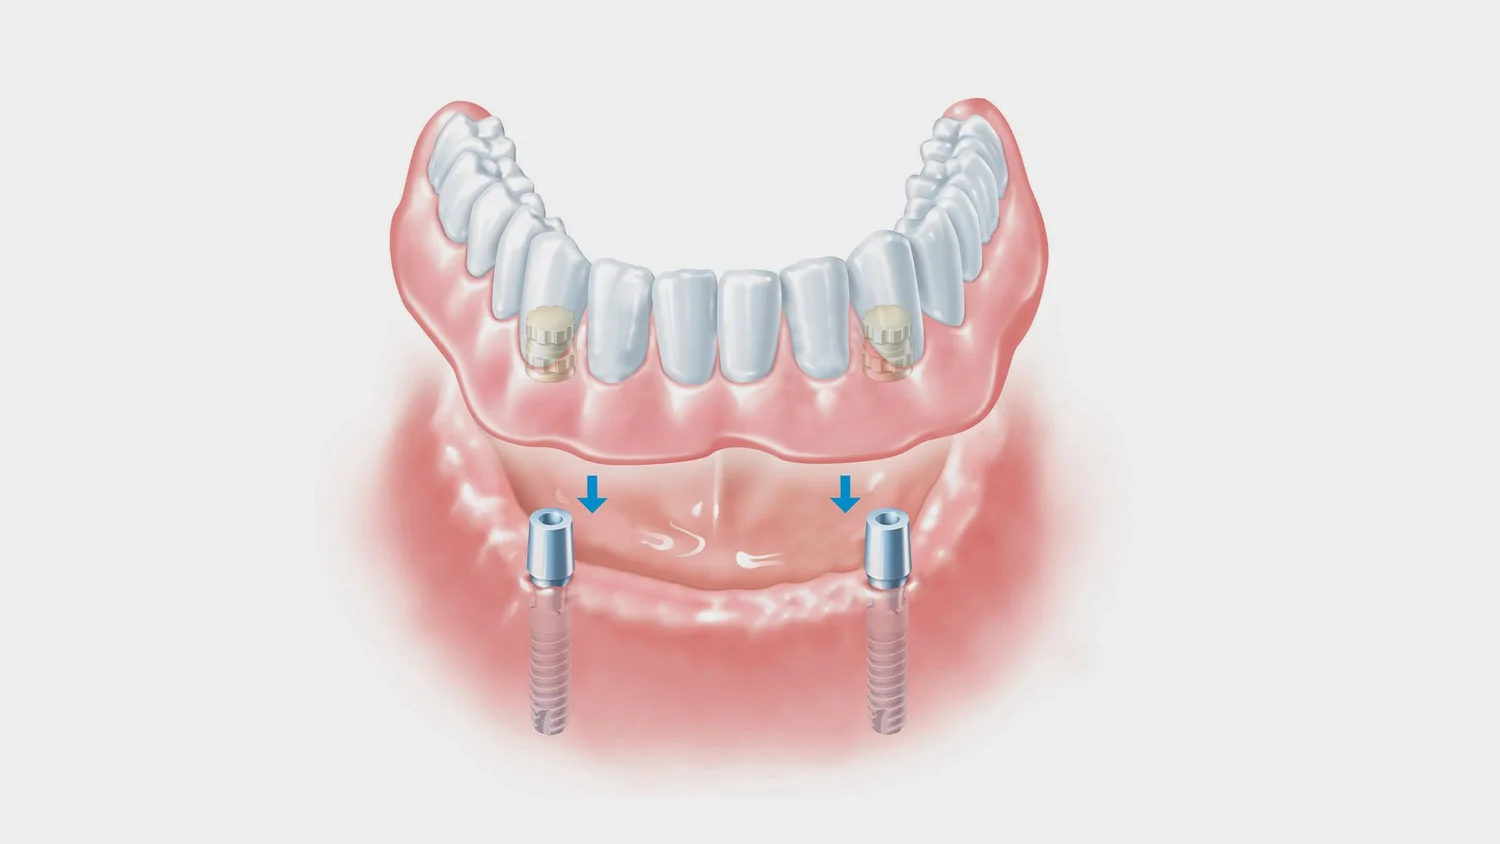

Overdentures are a type of removable denture that fits securely over remaining natural teeth or dental implants. Unlike traditional dentures that rest directly on the gums, overdentures are anchored in place to hard tooth tissue, providing significantly better stability and comfort.

They “snap on” to implants or prepared teeth, helping them stay firmly in place throughout the day.

1. Implant-Supported Overdentures

These are supported by dental implants placed in your jawbone. They offer the highest level of stability and function.